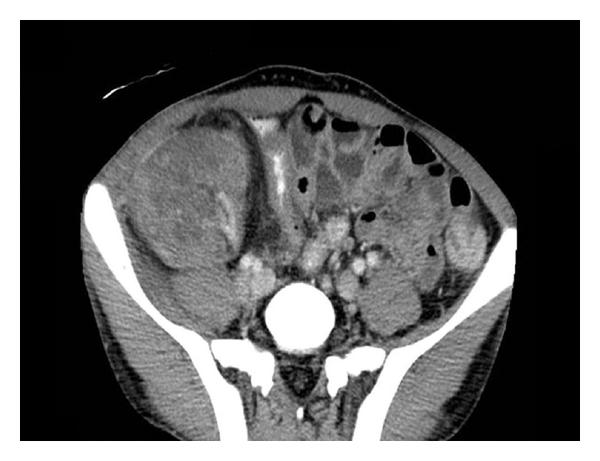

Two months later (65 months post renal transplant), the patient was admitted because of abdominal pain, graft tenderness, and gross haematuria. There was no history of abdominal trauma or recent renal allograft biopsy. Upon admission, the patient was pale, tachycardic, and hypotensive. His heart rate was 111 beat per minute, and the blood pressure 110/56 mmHg. Laboratory tests showed WBC of 2 × 103/μL, haemoglobin of 5.5 g/dL (dropped from 12.7 g/dL one month earlier), haematocrit of 16.6%, platelets count of 344 × 103/Ul, PT of 9.1, PTT of 33.9, BUN of 13.0 mmol/L, and serum creatinine of 809 μmol/L. The patient was resuscitated with crystalloid fluids and packed red blood cells. An enhanced abdominal computed tomography (CT) scan revealed few scattered hyperdense foci in the renal allograft, in keeping with microhaemorrhage and microperforations (Figure 1). The renal artery and vein were patent.